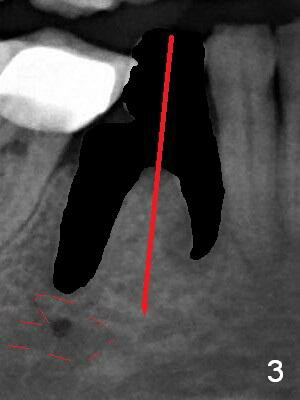

The patient returns for implant placement 11 months post extraction of #28 and 29. With flapless manner, initial osteotomy happens to drop into the original socket of #28 (Fig.4). After use of 3.3 mm Magic Drill (MD) and Final Drill for 15 mm, a 4x11 mm dummy implant is placed (Fig.5). It appears that the implant is long for the site (red dashed line: Mental Loop). However, a definitive implant (4x9 mm, IBS) has difficulty to reach its depth (Fig.6). After several rounds of untorque and retorque, the implant does not seat completely (Fig.7, implant driver disengagement) with autogenous bone placed distal (>). Retrospectively, a larger MD should have been used (3.8 mm) for complete seating in the dense bone. In fact she is post breast cancer treatment with 50% chance of relapse. The patient returns for follow up 1.5 months postop (Fig.8). The wound has healed. Impression is taken 5 months postop (Fig.9). When the crown is cemented, food impaction is an issue between the implant crown and crown at #30. Since the tooth #30 is mesially tilted with distal open margin and apical infection, the tooth will be extracted. Osteotomy is going to be initiated in the mesial slope of the mesial socket (Fig.9 red line). An implant will be placed more or less in the mesial socket (green box).